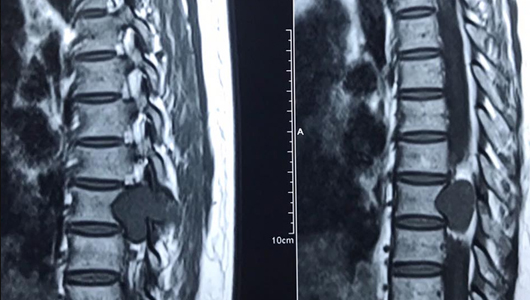

Lồi đĩa đệm L4 L5

L4 và L5 là vị trí xuất hiện tình trạng lồi đĩa đệm phổ biến hơn cả. Đây là các đốt sống thấp nhất trong toàn bộ cột sống thắt lưng. Chúng phải chịu những áp lực lớn nhất khi có bất kỳ một tác động nào đè lên cột sống. Do đó, sẽ có nhiều tổn thương xảy ra ở 2 đốt sống L4 và L5 này hơn, trong số đó chính là phồng lồi đĩa đệm. Tuy nhiên, tình trạng lồi đĩa đệm L4 và L5 vẫn có thể được coi là tình trạng phồng lồi nhẹ.

Lồi đĩa đệm L5 S1

Nếu như L4 L5 là các đốt sống nằm thấp nhất ở cột sống, thì L5 và S1 là 2 đốt sống được coi là điểm tựa chính của cột sống, đóng vai trò quan trọng giúp chúng ta thực hiện được những động tác phức tạp ở cột sống như cúi, ưỡn hay nghiêng người,... Việc hoạt động thường xuyên, thay đổi tư thế ở phần lưng sẽ khiến đốt sống L5 và S1 chịu nhiều tổn thương hơn nên dễ dẫn đến tình trạng lồi đĩa đệm.

Lồi đĩa đệm L5 S1 sẽ khiến đĩa đệm ở hai vị trí này Lồi và lồi ra sau, tuy nhiên nhân nhầy vẫn chưa thoát ra hẳn khỏi bao xơ. Do vậy sẽ gây ra một biến chứng khác, đó là bị thoát vị đĩa đệm. Loại lồi đĩa đệm này cũng khiến cho người bệnh cảm thấy đau nhức ở vị trí L5 S1, đồng thời hạn chế về khả năng vận động.